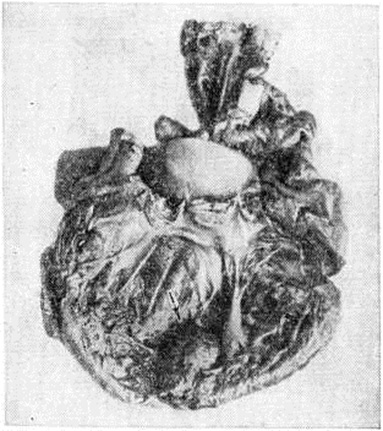

По характеру воспалительной инфильтрации (пролиферативный компонент воспаления) при интерстициальном (межуточном) Миокардит различают очаговый и диффузный варианты. При первом варианте клетки воспалительного инфильтрата располагаются в виде более или менее крупных, но ограниченных гнёзд (рисунок 4). При втором варианте клетки воспалительного инфильтрата диффузно пронизывают межуточную ткань миокарда, раздвигая сердечные мышечные волокна (рисунок 5), располагаясь вдоль них и охватывая различные по протяжённости участки миокарда. При диффузном Миокардит не обязательно тотальное поражение, охват воспалением всей массы миокарда, что бывает при острейшем, бурно развивающемся Миокардит Большей частью воспаление, даже диффузное, имеет мозаичный характер, поражая иногда избирательно или преимущественно субэндокардиальные слои миокарда. Можно предположить, что в начале развития такого Миокардит наблюдается расстройство микроциркуляции и проницаемости в терминальном сосудистом русле. Этот период, по-видимому, не бывает длительным и сменяется нарастающими экссудативными и пролиферативными процессами в строме миокарда.

|